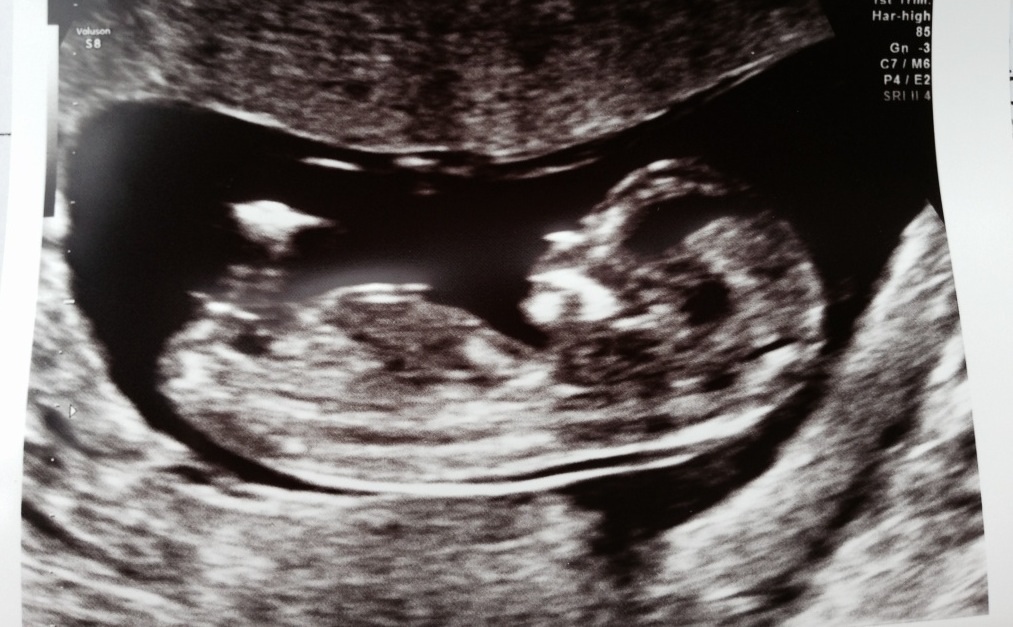

Clear nub shot ( I think?!) - guesses please. 13 weeks

Girl maybe?